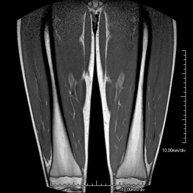

- Thigh MRI

Ideal examination for studying injuries to the hamstrings and quadriceps, which are frequently injured in athletes. It also allows for a good assessment of tendons and peripheral nerves. It lasts approximately 20 minutes. It is a radiation-free procedure.

- Leg MRI

Examination to study injuries to tendons, muscles and peripheral nerves. Very useful for diagnosing fibrillar tears in twins. It lasts approximately 18 minutes. It is a radiation-free procedure.